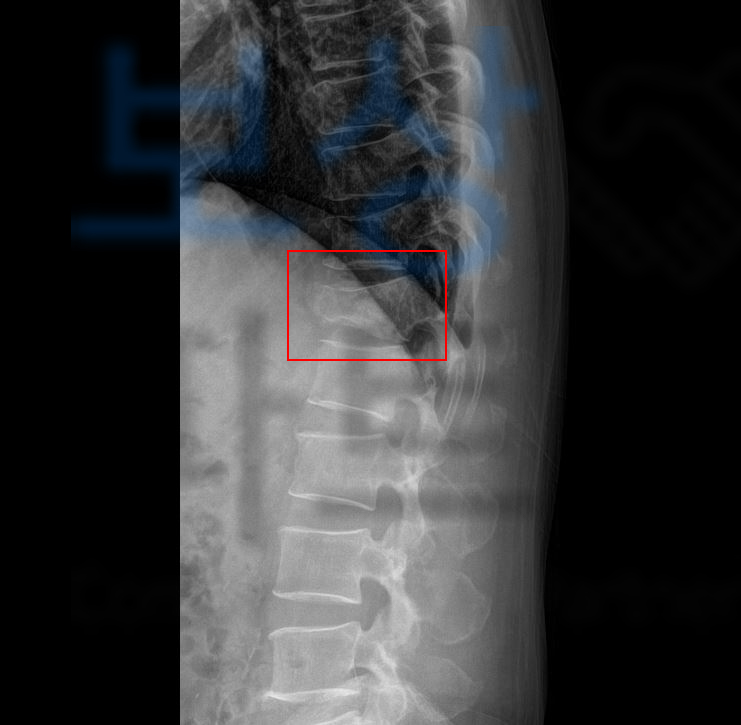

아프지 않고, 뼈가 잘 유합되었어도 척추골절의 특성상 원통 모양의 척추체가 무너지는 형태로 골절되기 때문에 척추가 기본적으로 가지고 있는 각도가 변형되기 시작하고 이러한 이유 등으로 보험약관상 “장해”에 해당될 수 있는 거죠.

영문으로 된 진단서를 풀어드리자면 C6-7 HCD -> 경추 디스크 S130 Bursting fx. T12 -> 흉추12번 척추골절 Acute comp.fx T11, L5, S2

-> 흉추11번 요추5번 천추2번의 급성 골절

환자의 흉추12번 척추골절 장해는 무려 뚜렷한 기형 30% 영구 장해에 해당하였습니다. 이후 흉추 12번 척추골절 장해에 대한 적정성을 증명하기 위해 손해 사정서 및 증빙자료를 각 보험사에 송부하였고 보험사에서도 조사관을 배정하여 내부 자문 및 의료자문을 시행하며 환자의 장해에 대한 면밀한 조사를 진행하였습니다.